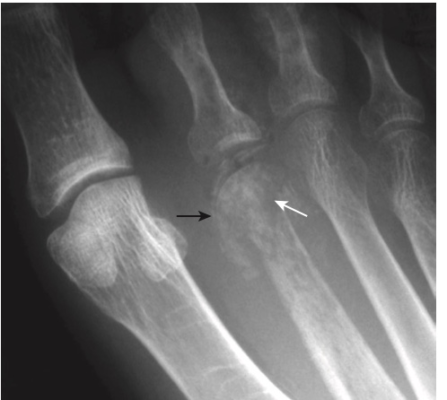

- Tiêu xương dưới màng xương, đặc biệt là ở mặt quay của đốt giữa của ngón trỏ và ngón giữa (Hình -2)